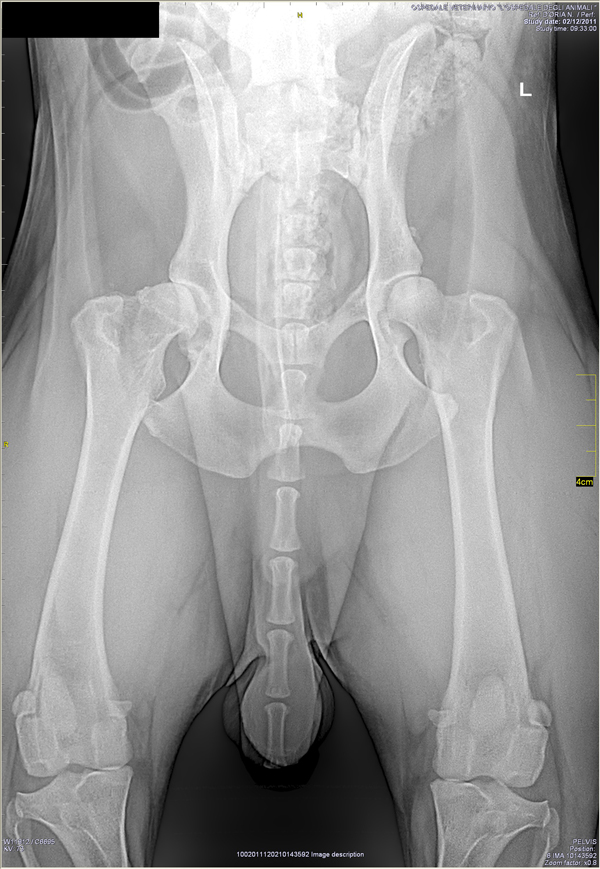

Displasia dell'anca di Pongo, cane Labrador Retriever |